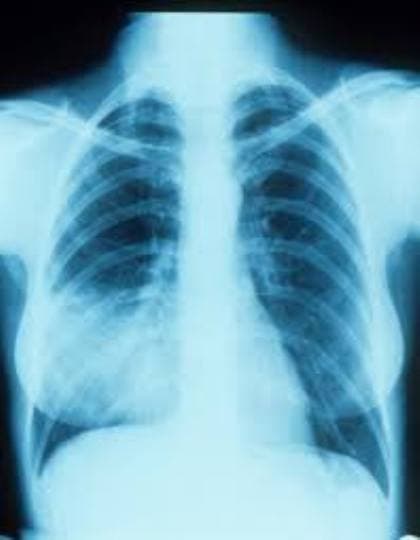

छह रोग, निमोनिया

बार-बार श्वास में संक्रमण